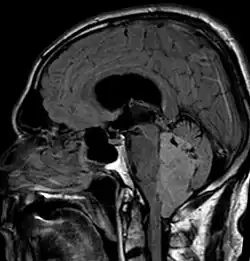

Ependymoma of 4.ventricle in MRI.

An ependymoma is a tumor that arises from the ependyma, a tissue of the central nervous system. Usually, in pediatric cases the location is intracranial, while in adults it is spinal. The common location of intracranial ependymomas is the floor of the fourth ventricle. Rarely, ependymomas can occur in the pelvic cavity.

Ependymomas make up about 5% of adult intracranial gliomas and up to 10% of childhood tumors of the central nervous system (CNS). Their occurrence seems to peak at age 5 years and then again at age 35. They develop from cells that line both the hollow cavities of the brain and the central canal containing the spinal cord, but they usually arise from the floor of the fourth ventricle, situated in the lower back portion of the brain, where they may produce headache, nausea and vomiting by obstructing the flow of cerebrospinal fluid. This obstruction may also cause hydrocephalus. They may also arise in the spinal cord, conus medullaris and supratentorial locations.[7] Other symptoms can include (but are not limited to): loss of appetite, difficulty sleeping, temporary inability to distinguish colors, uncontrollable twitching, seeing vertical or horizontal lines when in bright light, and temporary memory loss. It should be remembered that these symptoms also are prevalent in many other illnesses not associated with ependymoma.

Intracranial ependymomas, including supratentorial and posterior fossa, make up 90% of ependymomas in children. The supratentorial region is the upper brain region, or cerebrum, and contains the lateral and third ventricles. The posterior fossa, or infratentorial, is behind or below this region in the area of the brainstem and cerebellum and contains the fourth ventricle. A majority of intracranial pediatric ependymomas are in the posterior fossa.[15] Patients with intracranial ependymomas typically present with increased intracranial pressure that results in headaches, dizziness, nausea, and vomiting. The third location of ependymomas is within the central canal of the spinal cord. Spinal ependymomas comprise about 65% of adult ependymomas and most often occur in the lumbosacral region.[13] Patients with spinal ependymomas can present with back pain, numbness or weakness in the limbs, and urinary or bowel problems.